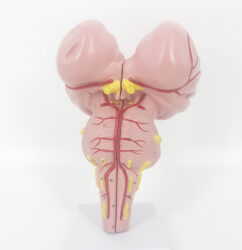

ATL-109 CHLID FEMORAL VEIN AND FEMORAL ARTERY PUNCTURE TRAINING SIMULATOR SOFT

This model is divided into internal carotid artery, carotid artery, subclavian vein and femoral vein and main arteries of femoral artery. Can be used for the injection of internal jugular vein, collarbone vein and femoral vein, blood and other targeted training and the practice of long catheter intubation. This model only can simulate the pulse of carotid artery, and femoral artery, but also can locate veins.

Packing: 1pcs/carton, 92x51x23cm, 10.5kgs